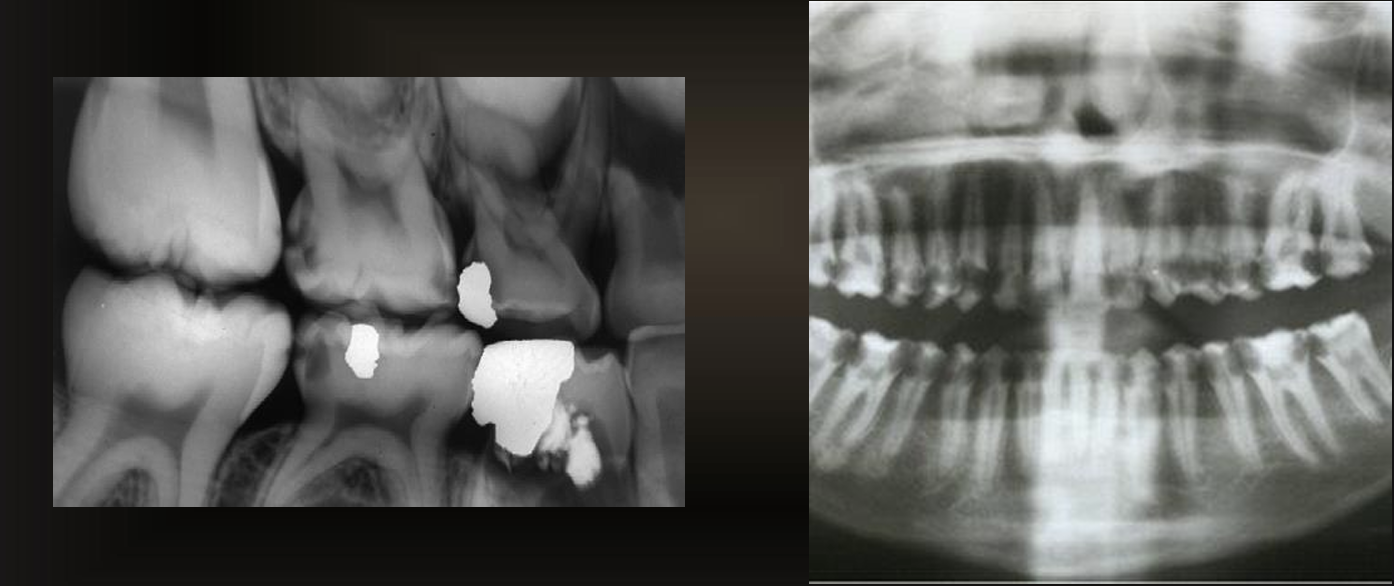

are these caries or restorations with radiolucent material?

caries

are these caries or restorations with radiolucent materials?

restorations with radiolucent materials

what do these images have?

recurrent caries

what are these arrows pointing at?

a restoration with a radiolucent liner- the box is too sharply defined to be a natural process (like secondary caries)